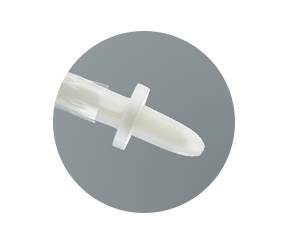

Beschermende inbrengtip

- helpt tijdens het inbrengen de steriele katheter te beschermen tegen bacteriën die zich in de eerste 15 mm van de plasbuis bevinden

- helpt het risico te verminderen dat bacteriën in de urinewegen terechtkomen

Bewezen bescherming tegen pathogenen – beschermende tip

De beschermende tip helpt het risico sterk te verminderen dat bacteriën tijdens het inbrengen in de urinewegen worden gebracht. Onderstaande illustraties tonen de effectiviteit aan bij gebruik bij mannen.

De katheter wordt tot in de tip geschoven, waarna de tip in de urethra wordt ingebracht.

De beschermende tip helpt voorkomen dat de katheter in contact komt met bacteriën die zich voornamelijk in de eerste 15 mm van de urethra bevinden.

De beschermende tip helpt voorkomen dat de katheter besmet raakt.